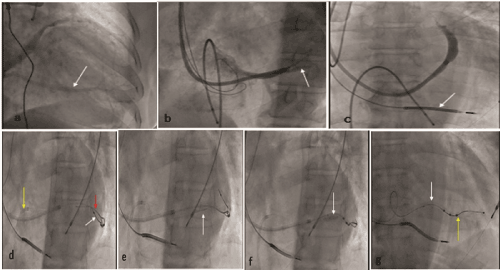

Figure 1. a. CS venogram showing a single large vein draining the posterolateral LV wall

b. Selective CS venogram showing a single tributary (arrow)

c. Deep hooking of catheter showed no further accessible veins

d. CS hooked with JR3.5 guide (yellow arrow) and CS tributary wired with SION BLUE wire (red); quadripolar LV lead is shown (white arrow)

e. Biomime 4.5X13 mm stent (arrow) placed proximal to quadripolar LV lead

f. Stent deployed at 10 atm

g. Final cine showed stent (white arrow) and intact quadripolar lead (yellow arrow)

Finally, the LV lead was stabilized by stenting the CS and jailing the LV lead, as there were no other alternative veins accessible for lead insertion (Figure 1c). Right femoral venous access was used using 6 Fr femoral sheath. A 6 Fr JR3.5 (LAUNCHER, MEDTRONIC) guiding catheter was used to access CS, and 0.014- inch coronary guidewire SION BLUE (ASAHI INTEC, Japan) was advanced into CS tributary (Figure 1d&1e). The average diameter of the CS tributary was 5 mm, so it was decided to stent with a 4.5 mm stent. Given the non-availability of a bare-metal stent, a drug-eluting stent was implanted in the CS tributary in a position 3cm away from the quadripolar lead, making sure not to damage the lead. A drug-eluting stent (DES) 4.5X13 mm (biomime™ MERIL) was deployed at 10 atm (Figure 1f&1g). The stent was deployed in the CS branch away from the main body of CS to prevent its occlusion. Post stent implantation, there was a good flow in the target vessel. Subsequently, catheters were removed without any LV lead dislodgement and there was no diaphragmatic stimulation. The procedure duration and mean fluoroscopy time were 137 min and 35 min, respectively. He was discharged after 3 days on dual antiplatelet drugs and optimal heart failure treatment. The QRS duration reduced to 110ms following CRT. He was under regular follow up with improved symptoms (NYHA class 1) and acceptable LV lead parameters of threshold and impedance of 1.5 V/0.4 ms, 900Ω respectively after 12 months.